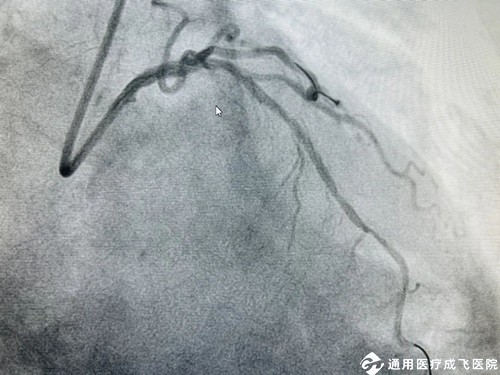

手术中,在王勉教授的指导下,心内科介入团队采用Shockwave 震波技术通过先后触发7个周期(70个脉冲)反复冲击波,以局部高效的震荡形式,对血管内的钙化结构进行“敲打”,在不影响正常血管组织的情况下将钙化结构碎裂,从而打开血管的“紧箍咒”,使血管扩张开,为后续的支架植入和充分扩张提供条件。术中前降支-左主干成功植入长支架1枚,历时仅1小时,病变狭窄明显缓解,管腔面积得到有效恢复,血流通畅。任大爷各项生命体征平稳,一直萦绕心头的“顽石”落了地,择期即将出院。

振波球囊后,血管明显扩张